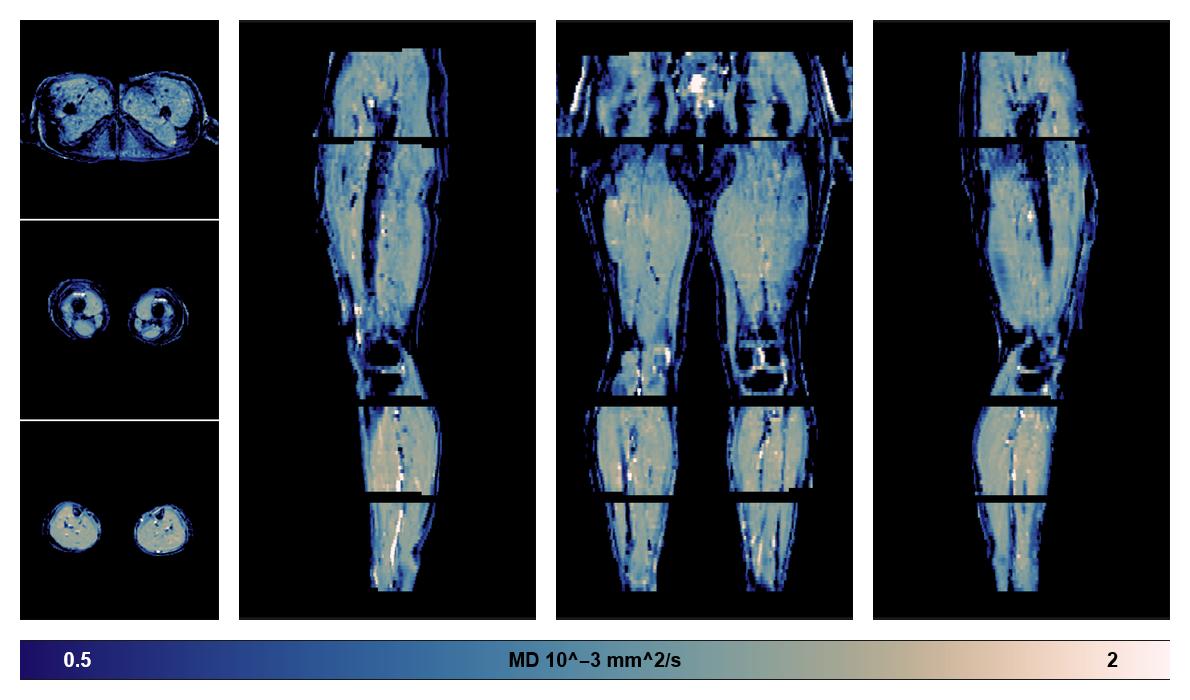

• Mean diffusivity

IVIM corrected whole leg muscle mean diffusivity obtained from diffusion tensor imaging.